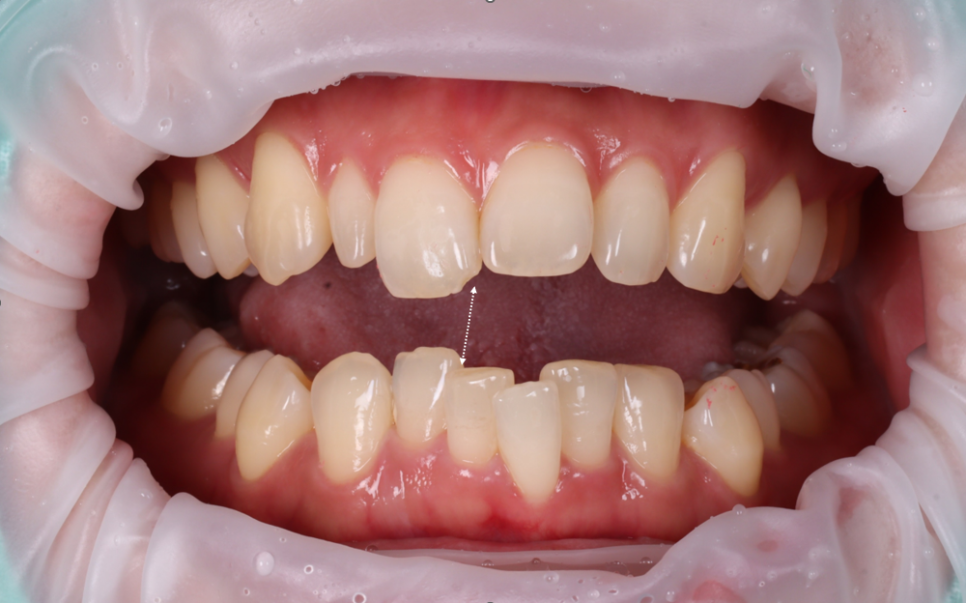

이번 환자분은 30대 여성으로 두 번째 앞니 한쪽만 왜소치였고, 더불어 가운데 앞니에 파절도 있었어요.

검진을 해보니 오른쪽 위 두 번째 앞니(측절치)는 전형적인 왜소치였고 반대편 두 번째 앞니는 크기와 형태가 정상이었어요.

문제는 치아가 ‘작다’는 사실 자체보다 양쪽의 균형이 깨져 있다는 점이었어요.

사람 얼굴이 그렇듯 치아도 좌우가 비슷해야 자연스러운데 한쪽만 유독 작으면 다른 곳들이 더 크게 보이거나 배열이 불규칙해 보일 수 있죠.

파절된 오른쪽 위 큰 앞니는 삐뚠 아래 앞니가 다물 때마다 부딪히는 형태였어요.

그래서 많은 힘을 받다 보니 치아의 끄트머리가 깨질 수밖에 없는 상황이었어요.